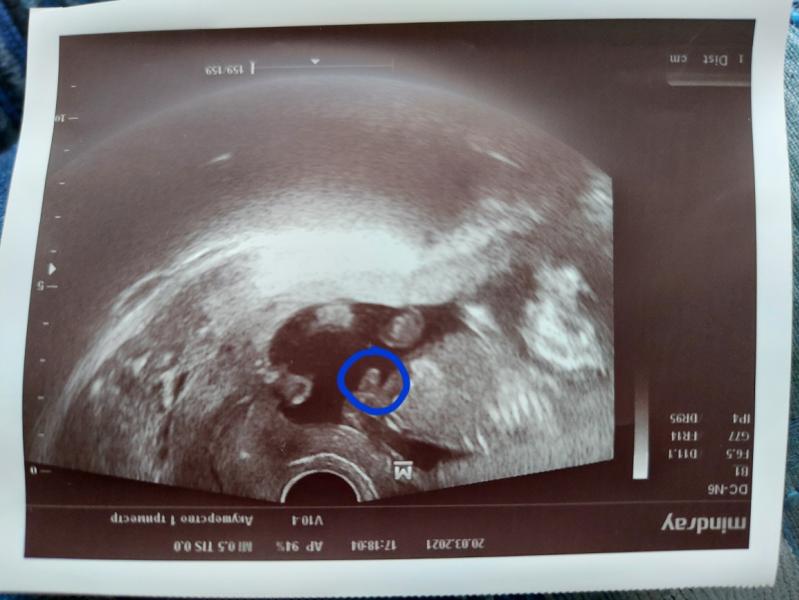

🔸️ На узи категорически показываться не хочет - то ручками лицо закрывает, то отворачивается спиной. Последний раз видела лицо на 1 скрининге. В конце мая 3D узи и боюсь, что он так и останется анонимом😅

Жаль мальчика нельзя назвать Соней😆 На всех узи дрыхнет, стучащие звуки его не будят)) Весь в мать, абсолютно нечутко сплю😄